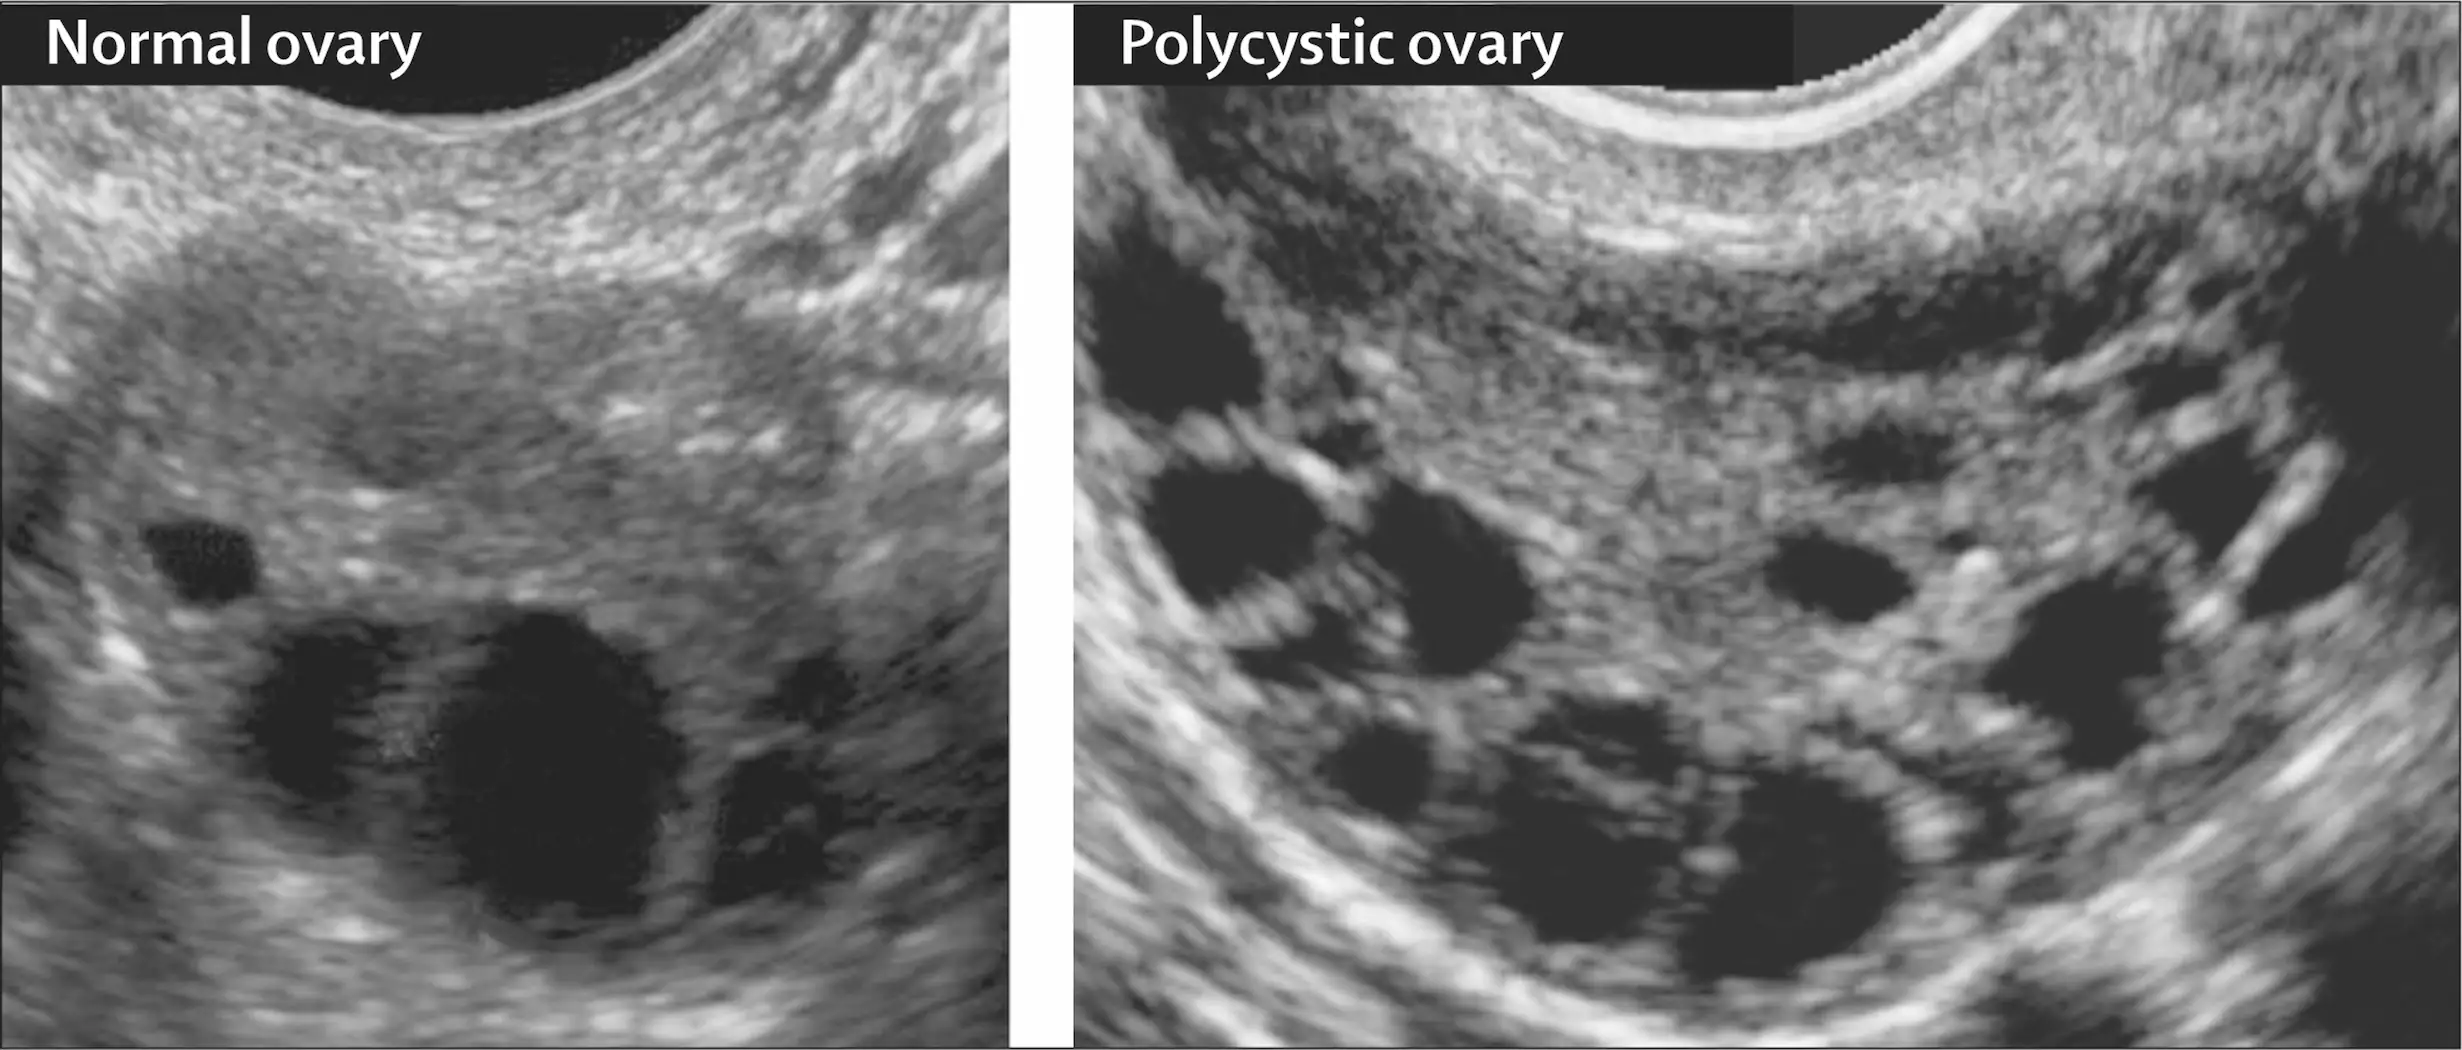

در سونوگرافی بعضی از خانمها، ممکن است کیستهای کوچک و ریز روی تخمدانها دیده شود. این کیستها در واقع تخمکهایی هستند که کامل رشد نکردهاند و آزاد نشدهاند.

اما نکته مهم این است که وجود کیست بهتنهایی دلیل قطعی PCOS نیست؛ یعنی ممکن است خانمی هیچ کیستی نداشته باشد اما همچنان مبتلا به این سندرم باشد.

5. سونوگرافی لگن:

پزشک از طریق سونوگرافی تخمدانها را بررسی میکند تا مشخص شود آیا کیستهای فولیکولی کوچک یا تخمدان بزرگ وجود دارد یا نه. همچنین ضخامت دیواره رحم نیز اندازهگیری میشود.